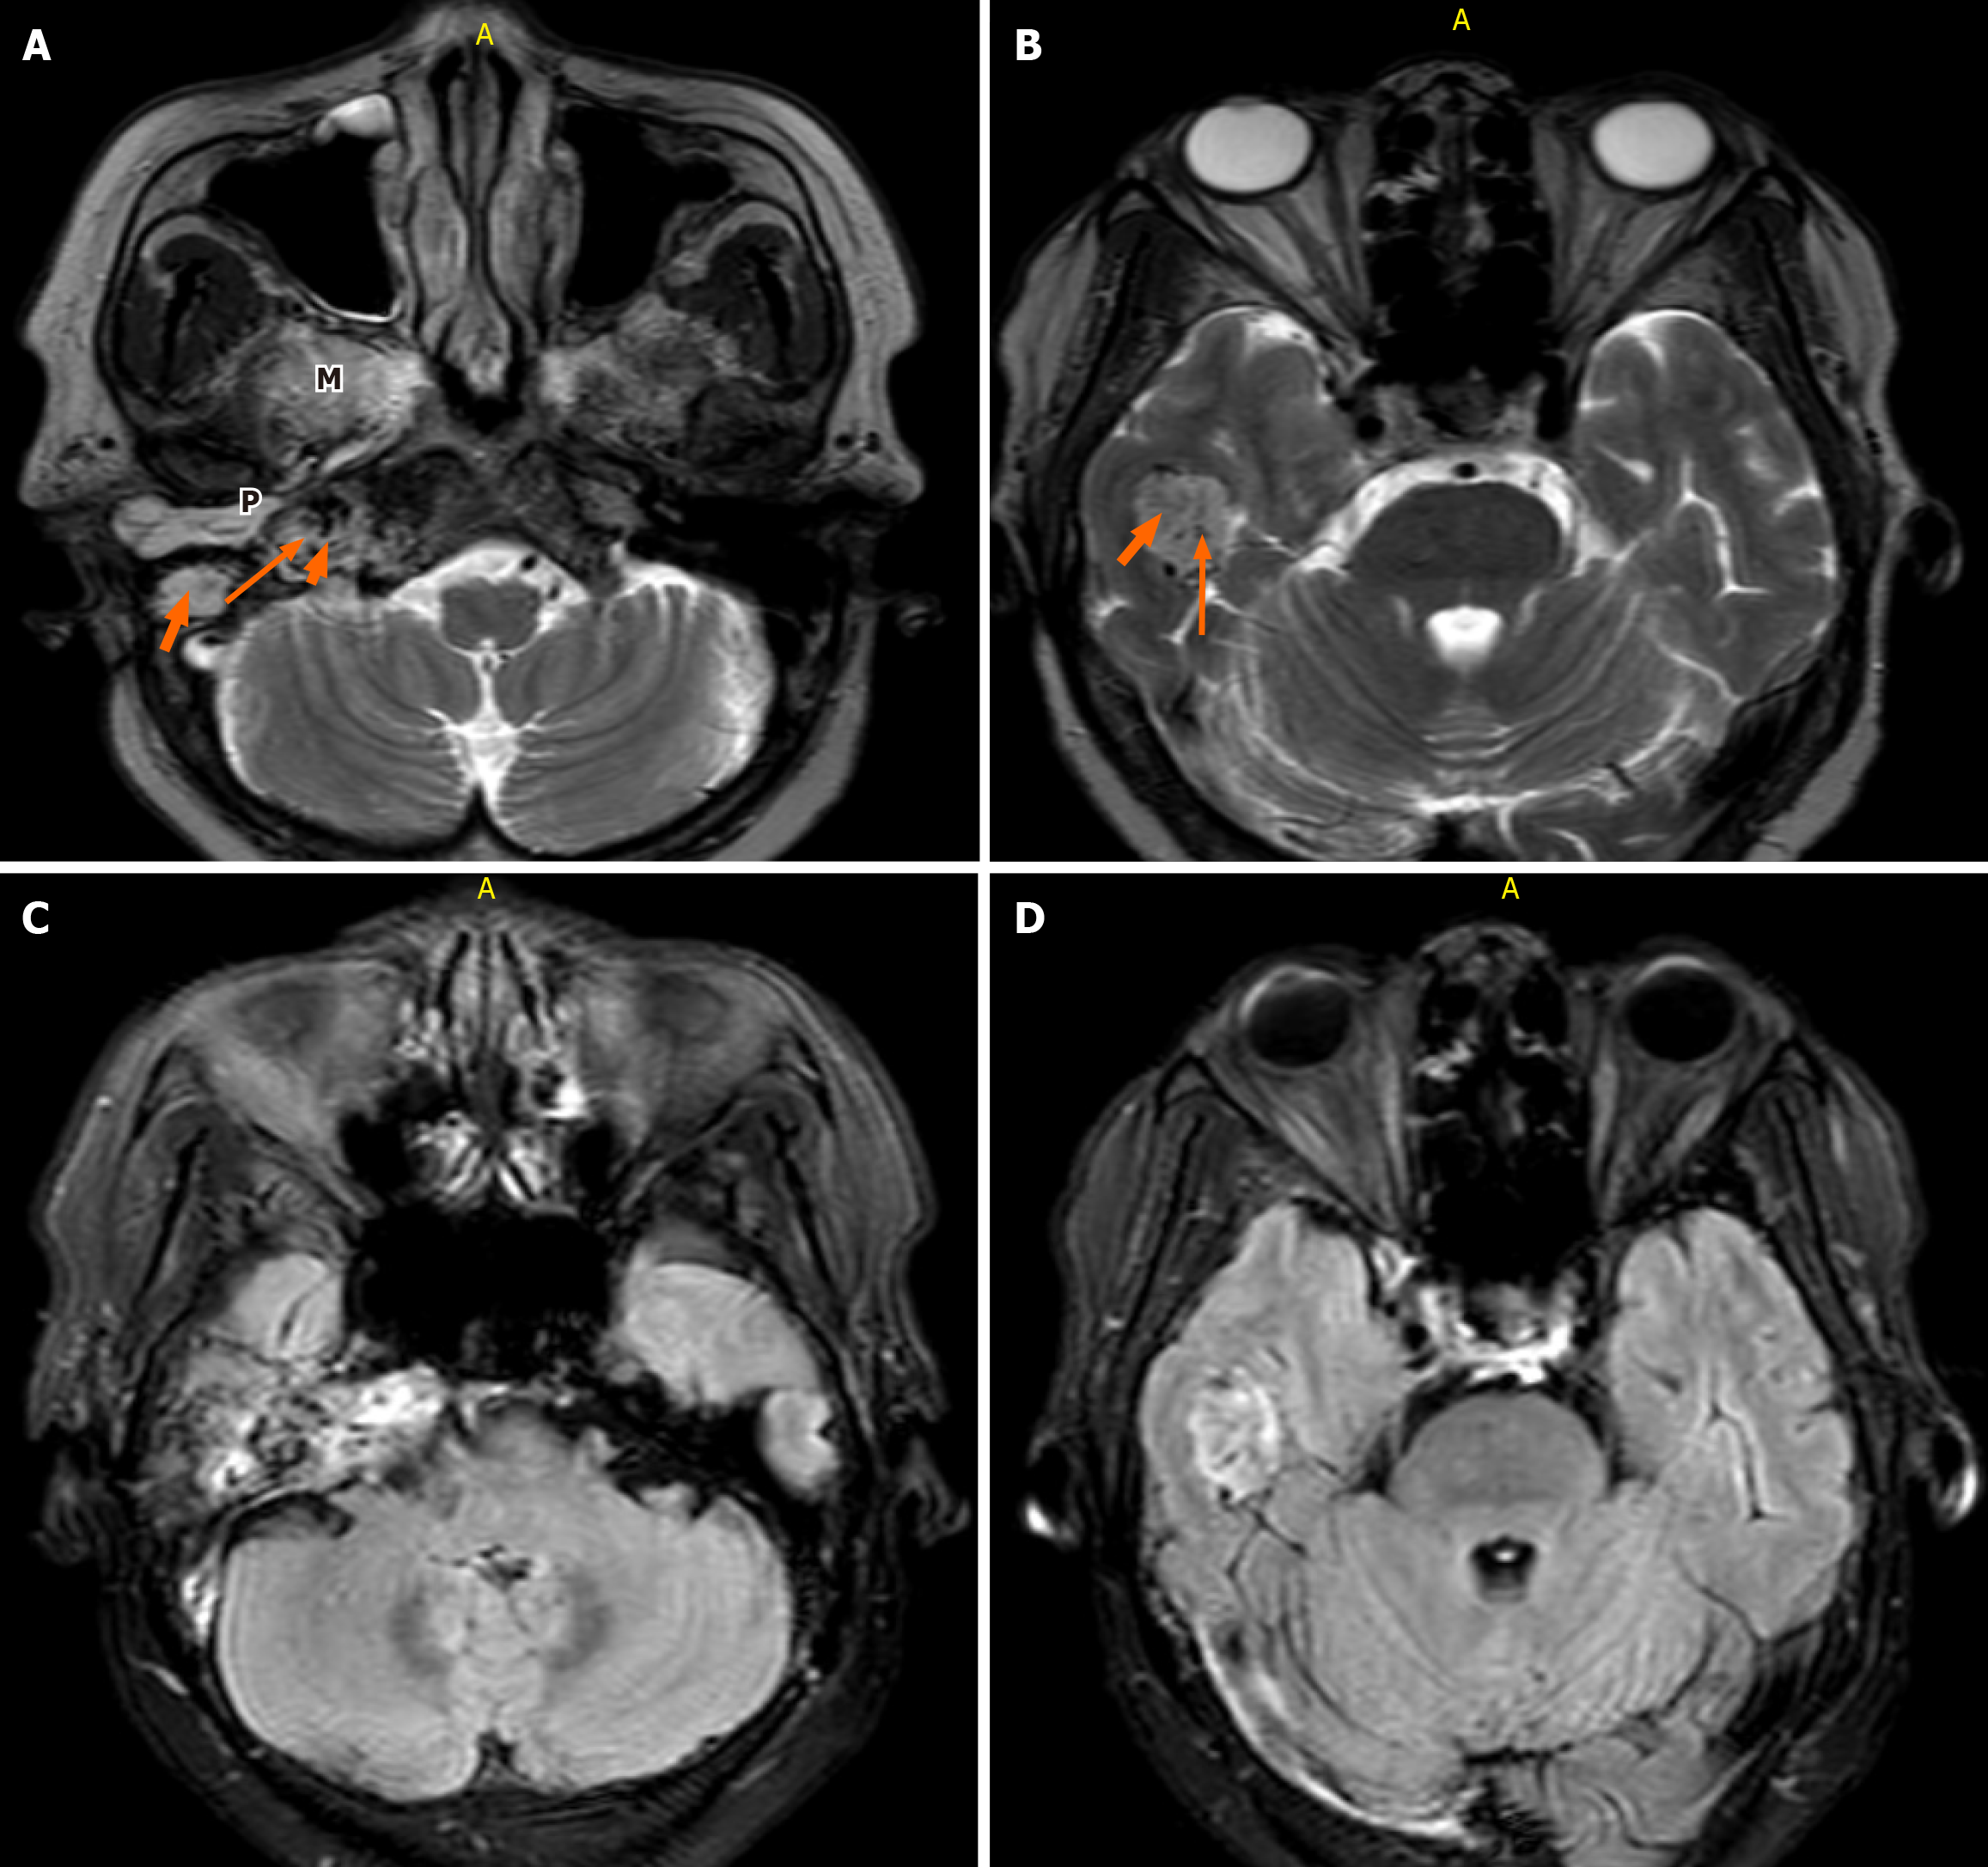

Figure 3 Axial non-contrast-enhanced T1-weighted magnetic resonance imaging of the brain (fast field echo sequence; repetition time 600 milliseconds, echo time 15 milliseconds, flip angle 25°, 3-mm slice thickness).

A and B: Of the brain demonstrates a poorly defined heterogeneous mass of slight hyperintensity and hypointensity centered at the right jugular fossa. A: Characteristic “salt” and “pepper” appearance is observed with punctate regions of hyperintensity representing the “salt” and small flow voids representing the “pepper” (long orange arrow and yellow arrow, respectively). Middle ear extension (thick short arrow) and masticator space (M) are seen; B: The right temporal lobe extension is demonstrated.

Figure 4 T2-weighted magnetic resonance imaging.

A and B: Axial T2-weighted magnetic resonance imaging of the brain (fast spin echo sequence; repetition time 4500-6000 milliseconds, echo time 90-110 milliseconds, 3-mm slice thickness) demonstrates a slightly hyperintense, heterogeneous mass in the region of the right jugular foramen (long arrow). A characteristic “salt and pepper” appearance is noted. The lesion extends inferiorly into the ipsilateral middle ear cavity (short thick arrow) and right masticator space (M), with superior extension into the ipsilateral temporal lobe (arrows). Hyperintense fluid signal within the right mastoid air cells indicates retained secretions (P); C and D: Axial fluid-attenuated inversion recovery magnetic resonance imaging shows a heterogeneous hypo- to hyperintense lesion involving the right jugular foramen and extending into the ipsilateral temporal lobe.